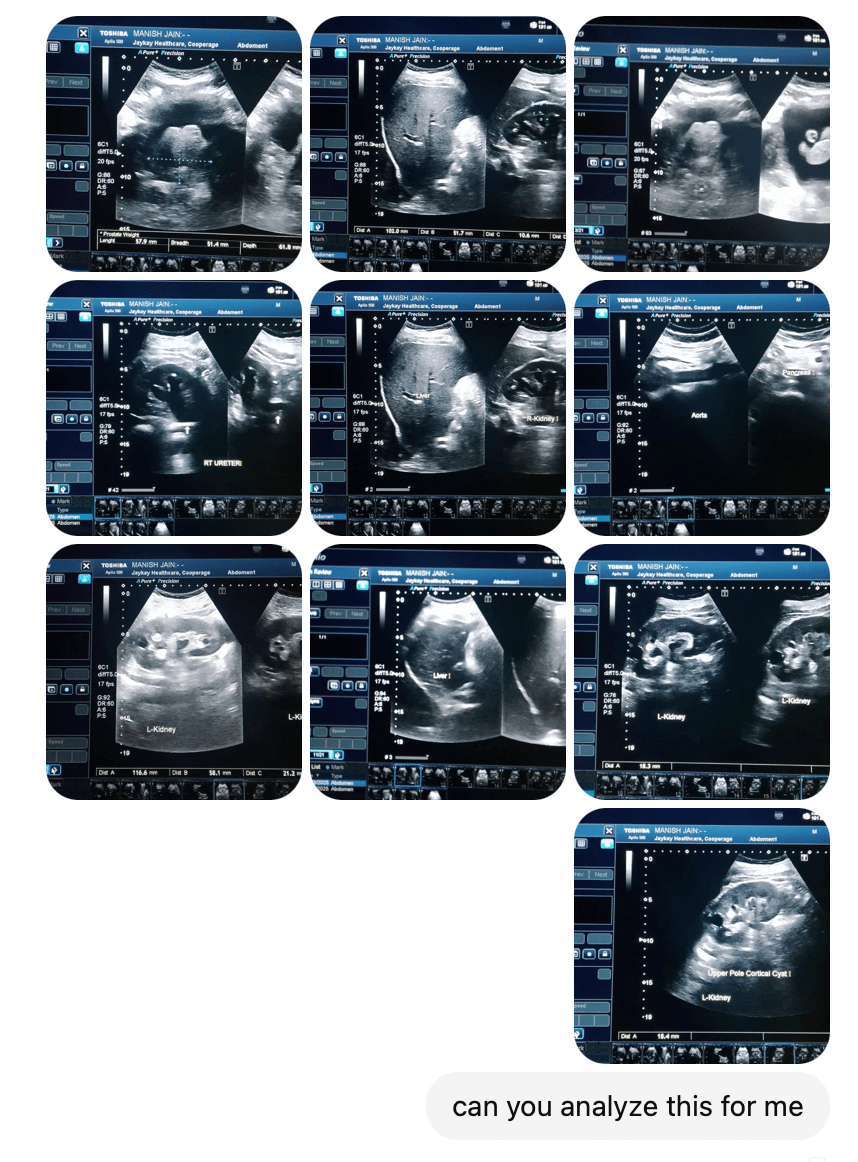

What ultimately led to my hospital admission started with an abdominal sonography. The doctor performing the scan immediately noticed abnormalities including an enlarged prostate, but told me I’d have to wait until the evening for the full report.

That wasn’t going to cut it. So I asked him if he could take 10–12 photos of the scan images directly from the computer screen and send them to me on WhatsApp. Surprisingly, he agreed.

Naturally, I took those grainy WhatsApp images and fed them straight into ChatGPT. Within a minute, ChatGPT analyzed the images, identified the size of my prostate, and offered an interpretation of what it thought the issue might be.

ChatGPT gave me an answer but did I really want to trust this “new fangled gadget?” The clarity and reassurance came later in the evening, when the official diagnostics report arrived.

What blew my mind was this: despite working off low-res WhatsApp images, ChatGPT’s analysis was astonishingly accurate when compared to a trained radiologist reviewing high-resolution scans. That was my first Whoa moment.